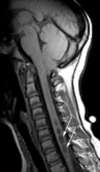

What disorder is found here?

Syringomyelia/Arnold-Chiari Type 1

What disorder is syringomyelia highly associated with?

Chiari Type I

What levels are syrinx formations generally found?

C2-T9